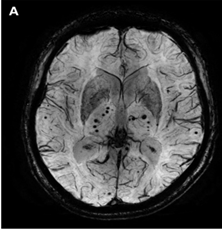

CAA是一種常見的腦小血管病,其特徵性病理改變為β-澱粉樣蛋白在大腦皮層和軟腦膜的小動脈及毛細血管壁內進行性沉積。磁共振T2WI或SWI顯示廣泛的皮質微出血或實質出血。

腦澱粉樣血管病相關炎症(CAA-ri)通常認為是軟腦膜及腦血管β-澱粉樣蛋白引起的炎症反應。典型的CAA-ri MRI表現為單灶或多灶不對稱白質高訊號(WMH)病變(皮質下或深部)延伸至皮質下白質,並伴有CAA相關出血併發症。通常在相關WMH附近觀察到大量的CMBs(圖1)。

圖1 CAA患者的T2WI(a-d)和FLAIR(e),可見皮質下微出血(a-c,白色箭頭)、亞急性晚期腦葉出血(c和e,黑色箭頭)、皮質鐵沉積(c和d,箭頭)、皮質下腦白質高訊號(WMH,e)、腦葉血管周圍間隙擴大(EPVS,e,箭頭)。